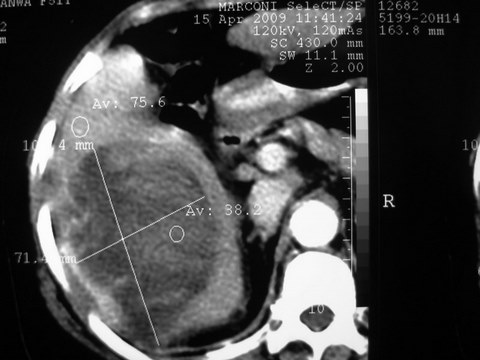

患者 女 51岁 两天前感觉上腹疼,无明显诱因,b超示肝右叶囊实性占位,边缘清楚,其内回声不均匀,ct增强如图,大家看看是什么 ,病人一年前及两月前b超检查只是提示胆囊炎

外院术后,证实肝癌合并出血

特点:1,病灶发展迅速,(2月前正常)[br] 2,囊实性,且并边界清晰光滑,呈右后叶赘生性。囊性区无强化,实性部分较多轻度强化,边界欠清。考虑囊腺癌或囊腺瘤。

出病理 中分化肝细胞癌合并出血